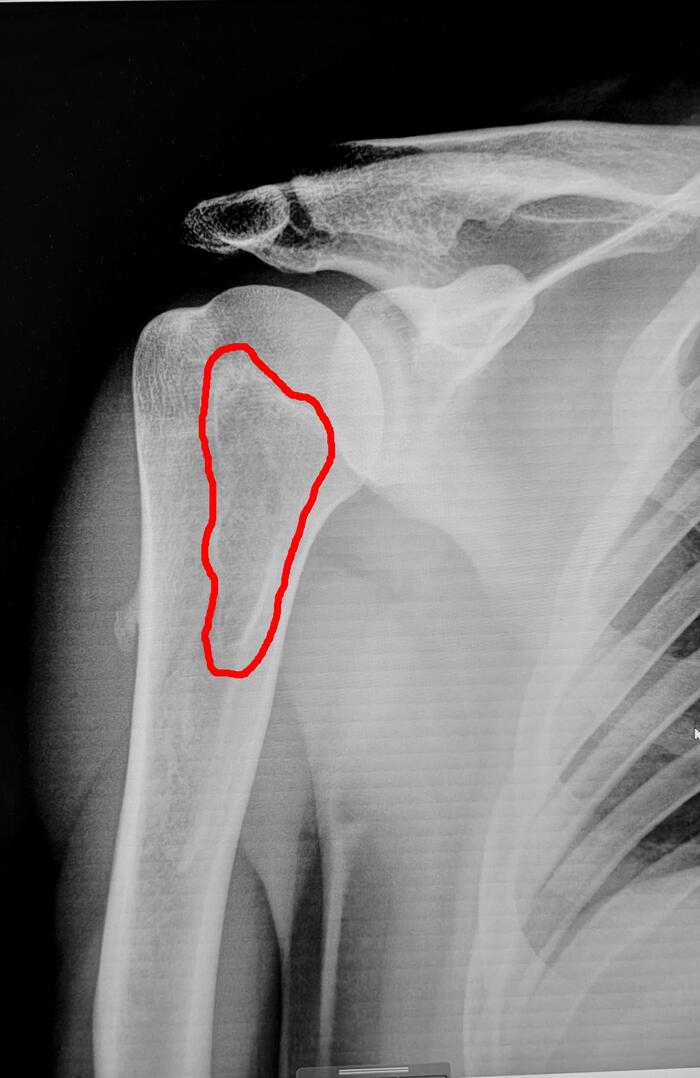

Описание снимка: на Р-грамме правого плечевого сустава в проекции проксимальной трети диафиза плечевой кости с переходом на головку плечевой кости визуализируется участок просветления костной ткани неправильной овальной формы, размером 12х3.5 см, с склеротическим ободком. Заключение: Костная киста правой плечевой кости.

При данной патологии применяется статья 10 (Доброкачественные новообразования (кроме доброкачественных новообразований нервной системы и мозговых оболочек), новообразования in situ:),для признания призывника негодным применяется такая формулировка: доброкачественные новообразования костной и хрящевой ткани, затрудняющие ношение военной формы одежды, обуви или снаряжения; с умеренным или незначительным нарушением функции.

Представленная выше киста ношению военной формы не препятствует, функции плечевого сустава не нарушает, однако данная киста достаточно крупного размера и при ее травматизации, чрезмерной нагрузке, может произойти патологический перелом плечевой кости.

Решение при данной патологии полностью на откупе у хирурга военкомата. Если следовать строго 565 постановлению-то это категория годности ст.10в-А2(годен к военной службе).,однако учитывая крупный размер кисты можно принять решение 10б-В(ограниченно годен к военной службе),все в руках хирурга.